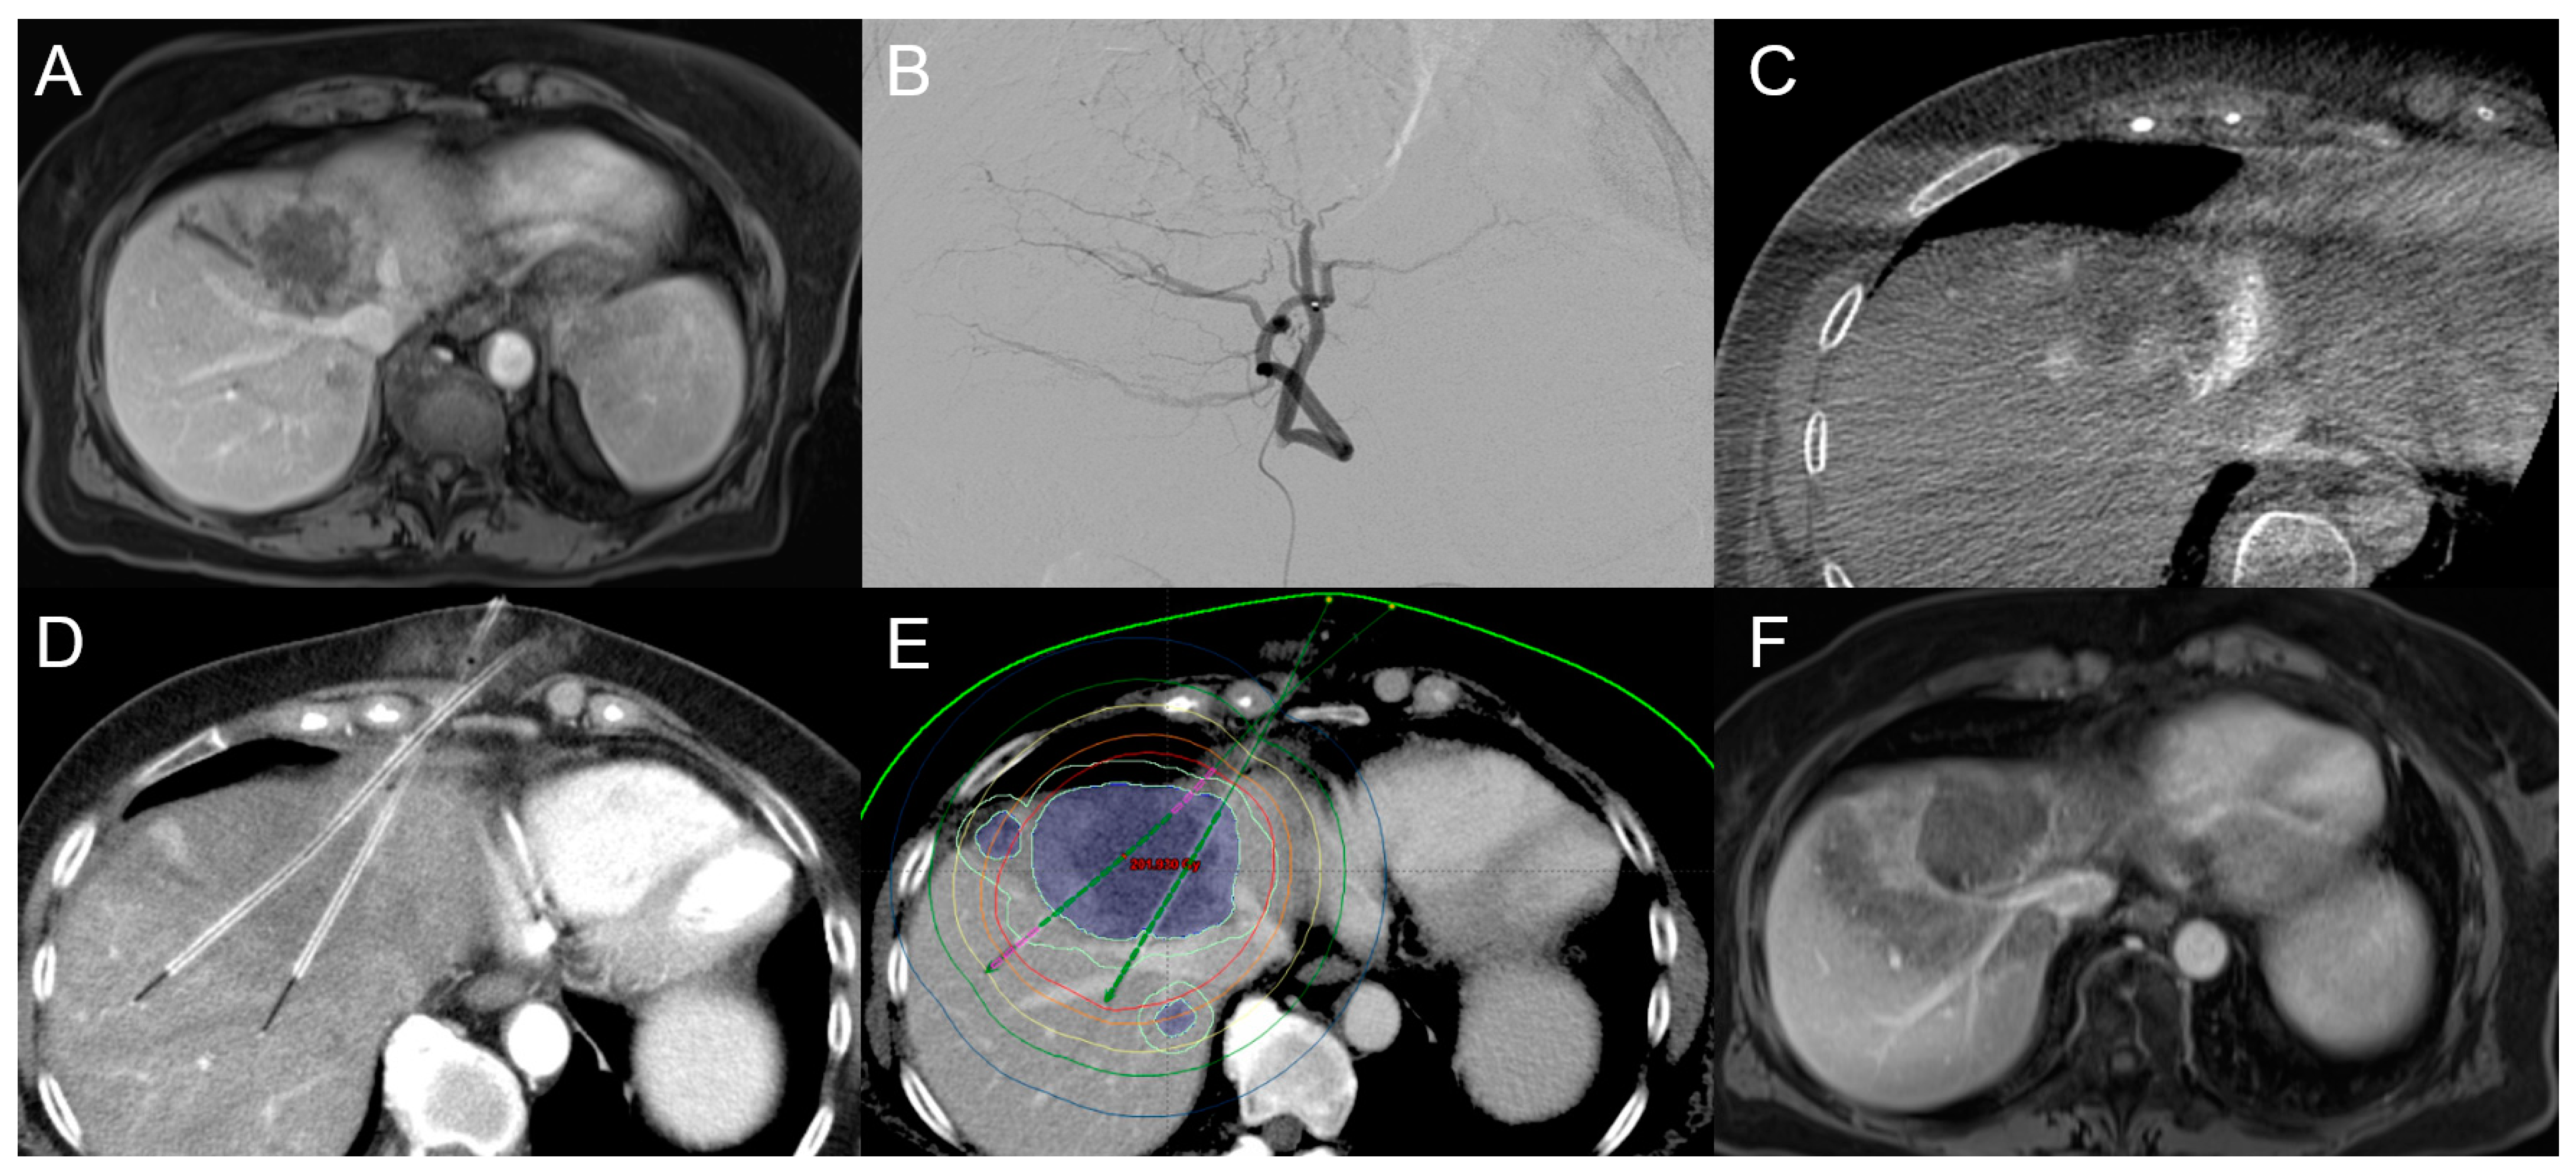

2.2.1. Computed Tomography High-Dose-Rate Brachytherapy (CT-HDRBT)

- Schnapauff, D.; Denecke, T.; Grieser, C.; Collettini, F.; Seehofer, D.; Sinn, M.; Banzer, J.; Lopez-Hanninen, E.; Hamm, B.; Wust, P.; et al. Computed tomography-guided interstitial HDR brachytherapy (CT-HDRBT) of the liver in patients with irresectable intrahepatic cholangiocarcinoma. Cardiovasc. Intervent Radiol. 2012, 35, 581–587. [Google Scholar] [CrossRef]

- Kamphues, C.; Seehofer, D.; Collettini, F.; Bahra, M.; Neuhaus, P.; Wust, P.; Denecke, T.; Gebauer, B.; Schnapauff, D. Preliminary experience with CT-guided high-dose rate brachytherapy as an alternative treatment for hepatic recurrence of cholangiocarcinoma. HPB 2012, 14, 791–797. [Google Scholar] [CrossRef]

- Jonczyk, M.; Collettini, F.; Schnapauff, D.; Geisel, D.; Boning, G.; Feldhaus, F.; Denecke, T.; Wieners, G.; Hamm, B.; Gebauer, B. Cholangiocarcinoma: CT-guided High-Dose Rate Brachytherapy (CT-HDRBT) for Limited (<4 cm) and Large (>4 cm) Tumors. Anticancer Res. 2018, 38, 5843–5852. [Google Scholar] [CrossRef] [PubMed]